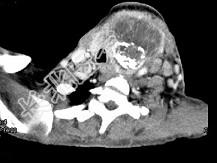

- 单项选择题女,64岁, 发现双甲状腺肿大1月余,CT如图所示, 最可能诊断是 ( )

A、甲状腺腺瘤

B、结节性甲状腺肿

C、甲状腺结核

D、甲状腺癌并淋巴结转移

E、甲状腺转移瘤